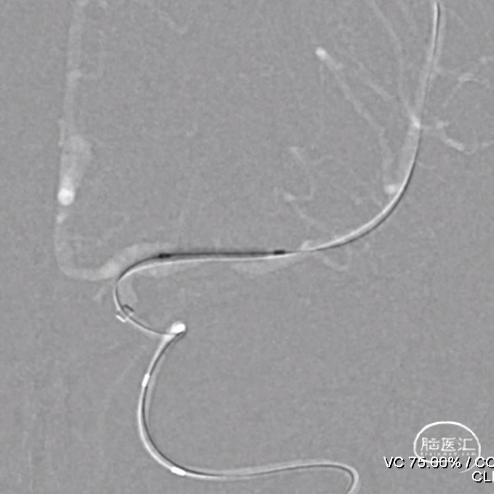

4、Neuroform® EZ定位释放

沿微导丝送入XT-27微导管,经微导管送入3.5mm*15mm Neuroform® EZ至狭窄处,定位后释放。

示意图

注意支架头端及尾端位置

Neuroform® EZ释放过程

5、 术后正侧位造影及3D造影

多角度投照显示支架帖壁良好,远端血管显影好,前向血流mTICI3级。